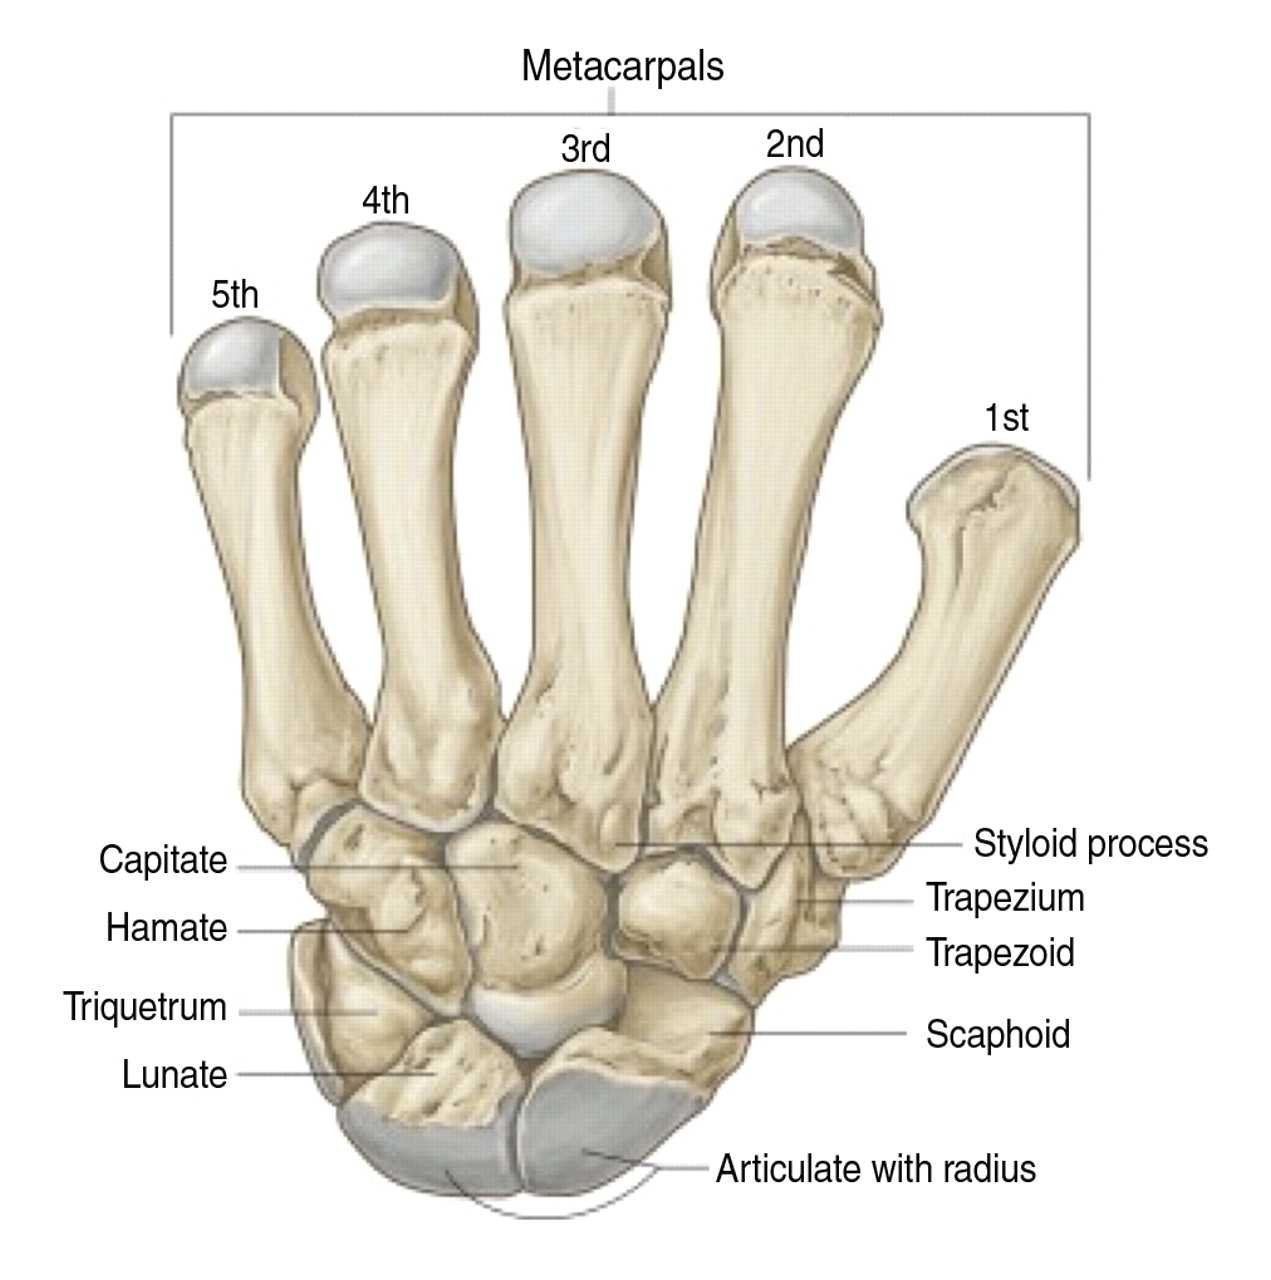

舟骨骨折是急诊中常见的损伤,占所有手部骨折的11%,占腕关节骨折的60%;舟骨表面80%被软骨覆盖,70%-80%的动脉供应由桡动脉分支提供,以逆行的方式进入背嵴。

舟状骨腰段骨折经皮固定技术

病人被置于仰卧位,在透视下,手被过伸牵引。这个位置扩大了舟骨和大多角骨的间隔,改善了对舟骨远极的可接近性(图1A和B)。在大多数情况下,纵向牵引足以复位骨折(在单独牵引不足的情况下,可使用克氏针作为操纵杆将骨折碎片操纵至其原始位置)。一旦通过透视检查确认复位,最重要的步骤是确定导丝的入口点和螺钉的位置。 这个入口点是舟状骨结节,它可以通过腕关节背身弯曲成90°,插入舟状多角骨关节的12-14号注射器针头定位。这根针头被撬入小多角骨,使舟骨的远端更为偏桡侧,有助于导丝的插入(图1C)。

图1

经皮腕舟骨腰段骨折的治疗。

A、 影像增强器相对于要手术的手的位置;

B,手腕过度伸展,以显示舟骨的入口点和真(纵向)轴;

C,手腕过度伸展时的克氏针入口点;

D,在侧视图上沿舟骨真实轴插入克氏针;

E,沿舟骨真轴插入克氏针,前后位和侧位视图;

F,沿舟骨真轴拧入螺钉。

理想的起点距离舟状骨结节顶点约2毫米(以实现骨路径内的最大导丝长度) 。一旦确定了方向和入口点,导针就被置入到关节中,这样碎片就不会在导丝通过过程中移动。引入导丝,并通过图像增强器连续评估其方向,以便将导丝送到近端(图1D和E)。如果导丝处于满意的位置,做一个大约0.5cm的纵向切口,用止血器探查,直到舟状骨结节。 螺钉的长度由测深确定,短4–5 mm以获得正确的测量值 。 在少数情况下,可以使用第二根克氏针以避免碎片旋转。 取下针头,用空心钻穿过导丝,距关节面约2 mm。压缩螺钉穿过导丝,并用图像增强器检查其末端位置。然后关闭切口(图1F)。

舟骨近端三分之一骨折的经皮固定技术

将患者置于仰卧位,手臂伸直放在手术台上。影像增强器垂直于手腕放置。为了导丝的通过,在将舟状骨的中心轴定位在前后视图上之后,手腕旋前并弯曲45度或更大,直到舟状两极进入直线(图3A)。